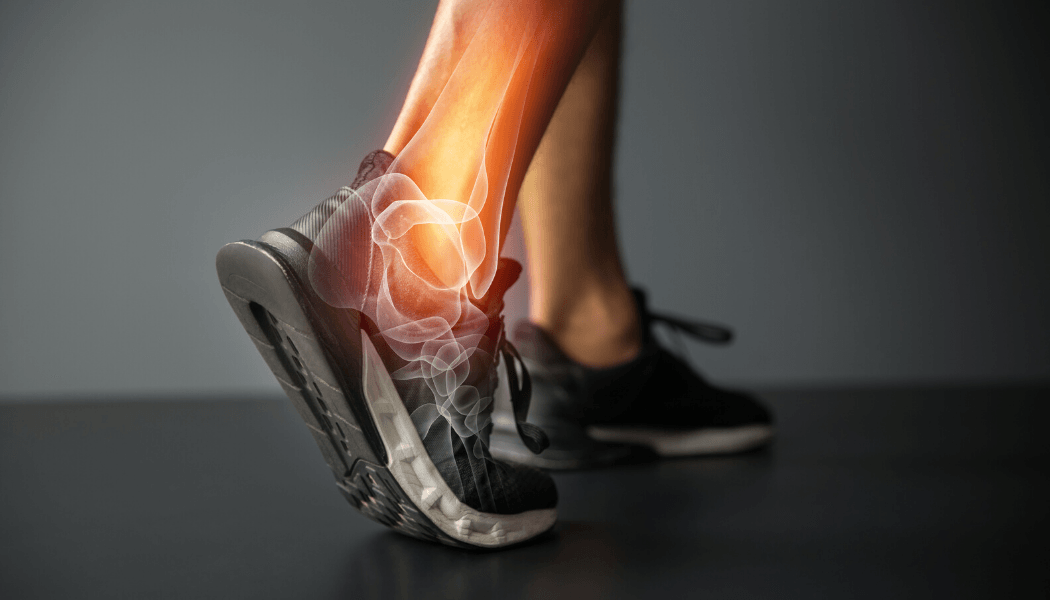

Ankle Pain

The ankle joint is a hinge type joint that resides at the distal part of the lower limb. It is formed by the talus (a bone of the foot), the lateral malleolus (bony end of the fibula on the outside of the ankle) and the medial malleolus (the bony end of the tibia on the inside of the ankle.

There are numerous ligaments in and around the ankle joint, both on the inside and outside that help to provide stability. The ligaments on the outside of the ankle are commonly injured when the sole of the foot roles inwards.